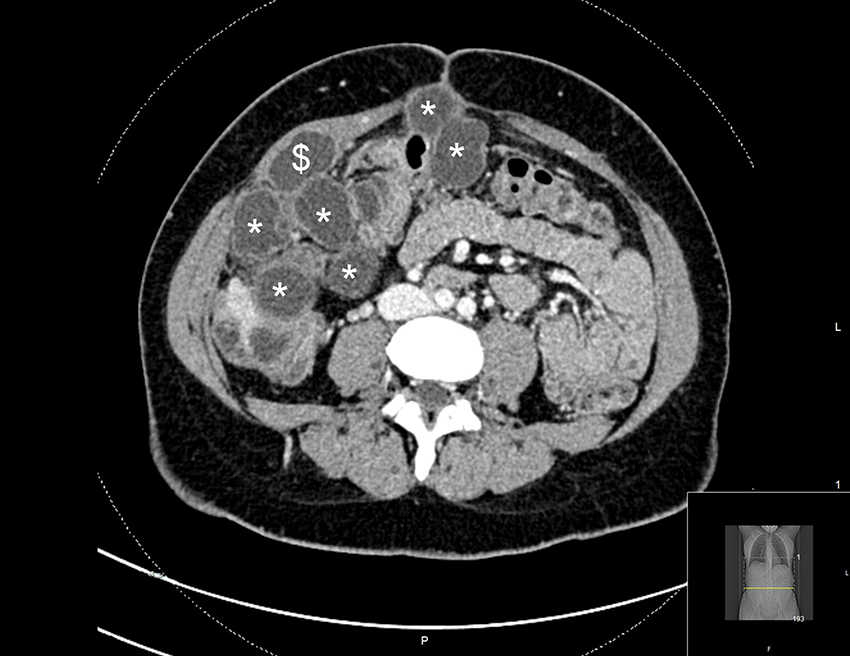

En kvinne i 30-årene hadde noen år tidligere fått påvist en solitær levercyste i forbindelse med utredning for magesmerter. Cysten ble behandlet med perkutan drenasje og sklerosering. Grunnet raskt residiv ble det utført kikkhullskirurgi med delvis fjerning av cysteveggen (laparoskopisk fenestrering) tre måneder senere. Cysteveggen ble sendt til histopatologisk undersøkelse, som ikke viste patologi i veggen eller parasittsykdom. Fra tidligere hadde pasienten diabetes mellitus type 1 og ulcerøs kolitt. Blodsukkeret var velregulert med insulinpumpe. To år etter fjerning av cysteveggen var hun fortsatt plaget med magesmerter. CT viste tallrike cyster i leveren og bukhulen fra diafragma til bekkenbunn (figur 1). Mistanken om parasittinfeksjon ble reist på nytt, og regranskning av cysteveggen fra operasjon to år tidligere var forenlig med dette. Serologisk prøve bekreftet infeksjon med parasitten Echinococcus granulosus.

To cyster var utilgjengelige for reseksjon uten omfattende organreseksjon. Disse ble først aspirert, deretter ble hypertont saltvann instillert før fenestrering og uthenting av dattercyster (figur 2). Under operasjonen rumperte to cyster spontant. Grunnet cysteruptur ble bukhulen avslutningsvis skylt med 2 liter hypertont saltvann i ti minutter. Saltvannet ble sugd ut, og bukhulen ble skylt i to runder med fysiologisk (0,9 %) saltvann. Pasienten var stabil under inngrepet, men var pressorkrevende. Operasjonen varte i totalt 12 timer.